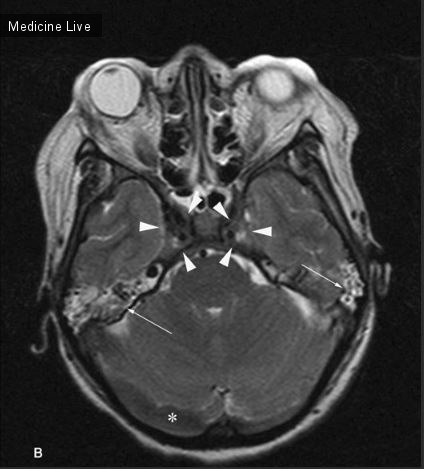

Тромбоз синусов вен

Тромбоз синусов вен 116 фотографий